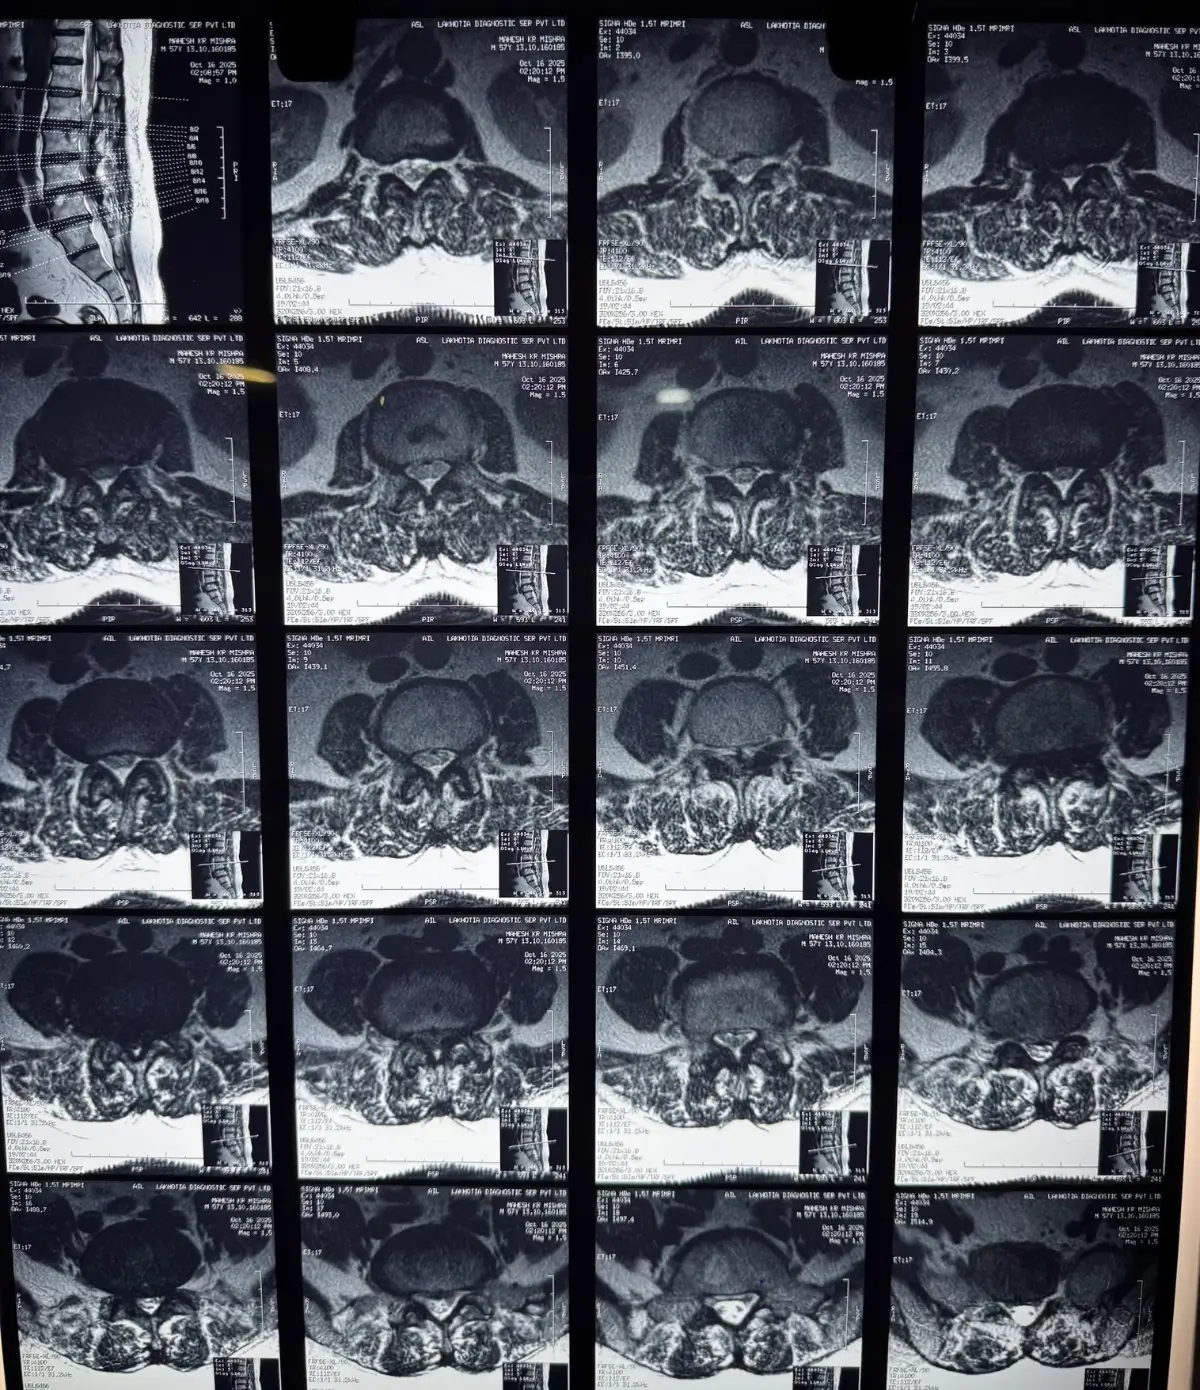

A 57 yr old morbid #obese Man with severe #LowBackPain and radiation pain along both lower limbs. In such cases often neural foramens of affected nerve roots are compressed along with the compromised spinal canal. Just #posteriordecompression may not be sufficient to give him back #activelifestyle, that is the reason the #vertebralcolumn was anteriorly stabilized with #PEEK cages and #bonegraft by #PLIF method along with posterior pedicle screw fixation #SpineSurgery #theboneclinic #drraysboneclinic